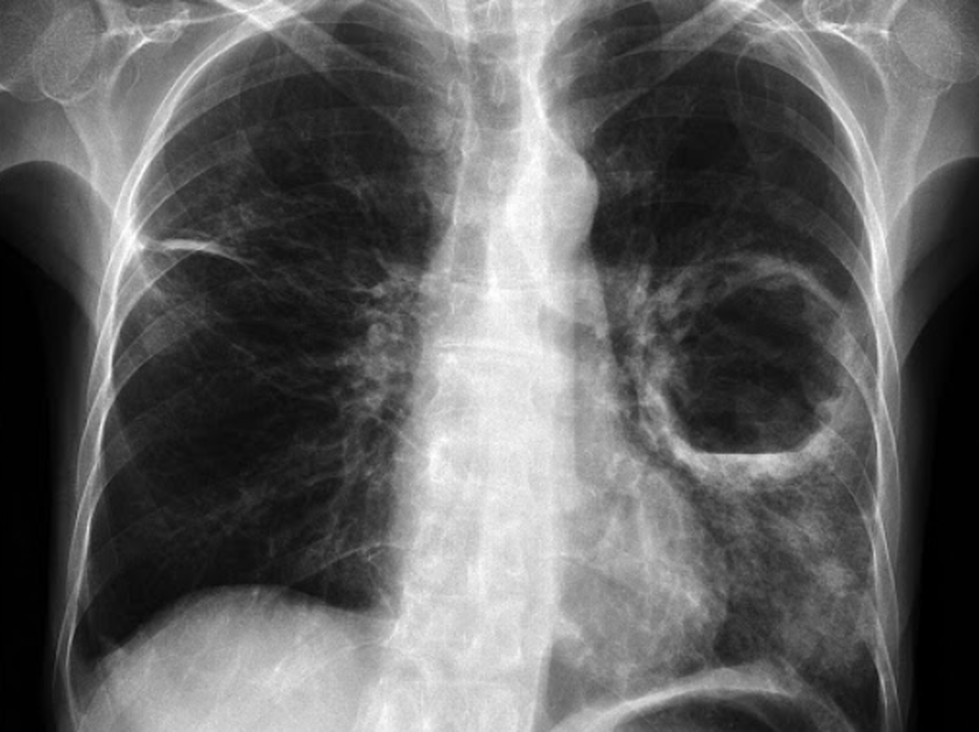

Chụp X-quang, CT hoặc MRI: Quan sát được kích thước khối áp xe và kiểm tra vùng xung quanh phổi có bị tổn thương hay không.